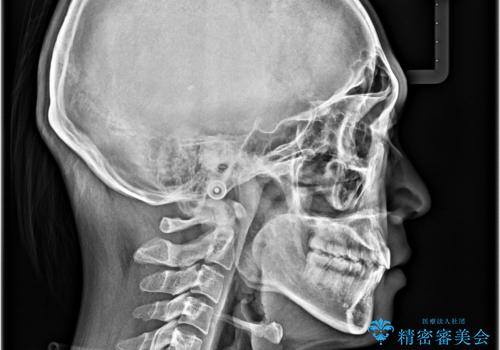

- 八重歯と口元の閉じにくさを気にして来院された患者様です。

非抜歯矯正で歯列を整えると、治療後に口元が今よりも突出する可能性が高かったため、上下左右の第一小臼歯4本を抜歯し、ワイヤー装置にて矯正治療を行うこととしました。